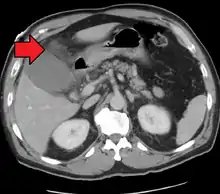

Acute cholecystitis with gallbladder wall thickening, a large gallstone, and a large gallbladder- Significant gallbladder wall thickening[29]

- Significant gallbladder wall thickening[29]

Right upper quadrant abdominal ultrasound is most commonly used to diagnose cholecystitis.[1][26][27] Ultrasound findings suggestive of acute cholecystitis include gallstones, pericholecystic fluid (fluid surrounding the gallbladder), gallbladder wall thickening (wall thickness over 3 mm),[28] dilation of the bile duct, and sonographic Murphy's sign.[13] Given its higher sensitivity, hepatic iminodiacetic acid (HIDA) scan can be used if ultrasound is not diagnostic.[13][14] CT scan may also be used if complications such as perforation or gangrene are suspected.[14]